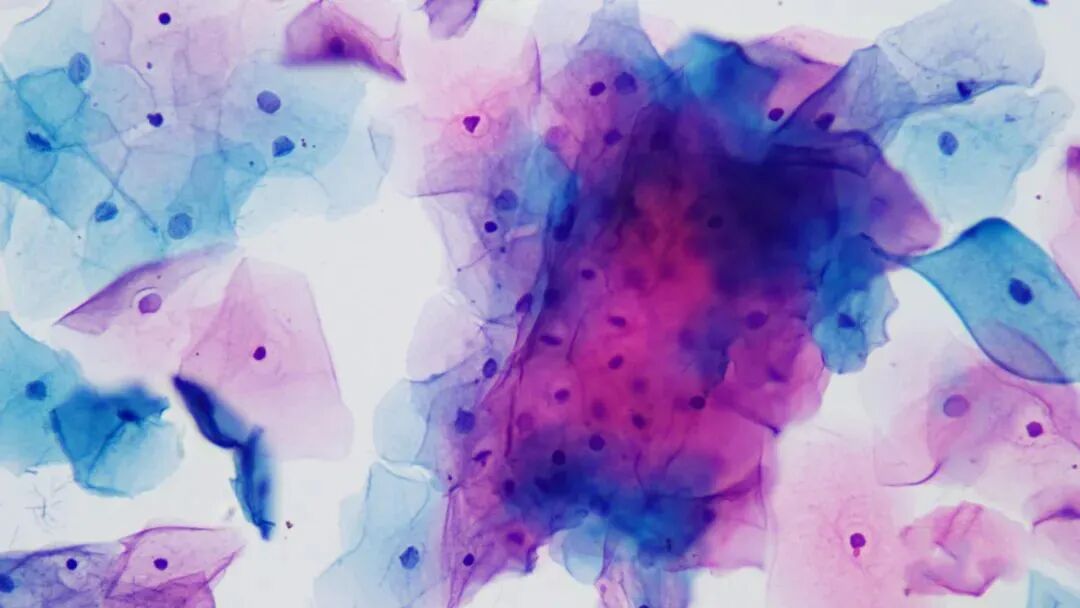

中表层成团,部分细胞也皱缩没有展开,这些都不利于诊断。

细胞成团趋势过多,红蓝绿对比较差。

中表层成团没有散开,而腺上皮团过于厚重以至于看不清核。散开的细胞也容易皱缩影响诊断判读。

成团对病理医师影响还是比较大的,右侧中表层细胞还好,左侧这个腺上皮细胞团就根本看不清核。同时这几张片子还有蓝绿染色过深,红绿蓝对比不鲜明。

下面看看调整后不同激素水平液基片:

低倍整张片子均匀平铺,蓝绿红对比鲜亮。

高倍

中低倍

这个时候再观察成团细胞基本上毫不费力,而且微螺旋调节焦距时腺上皮各个细胞层次均清晰可见。